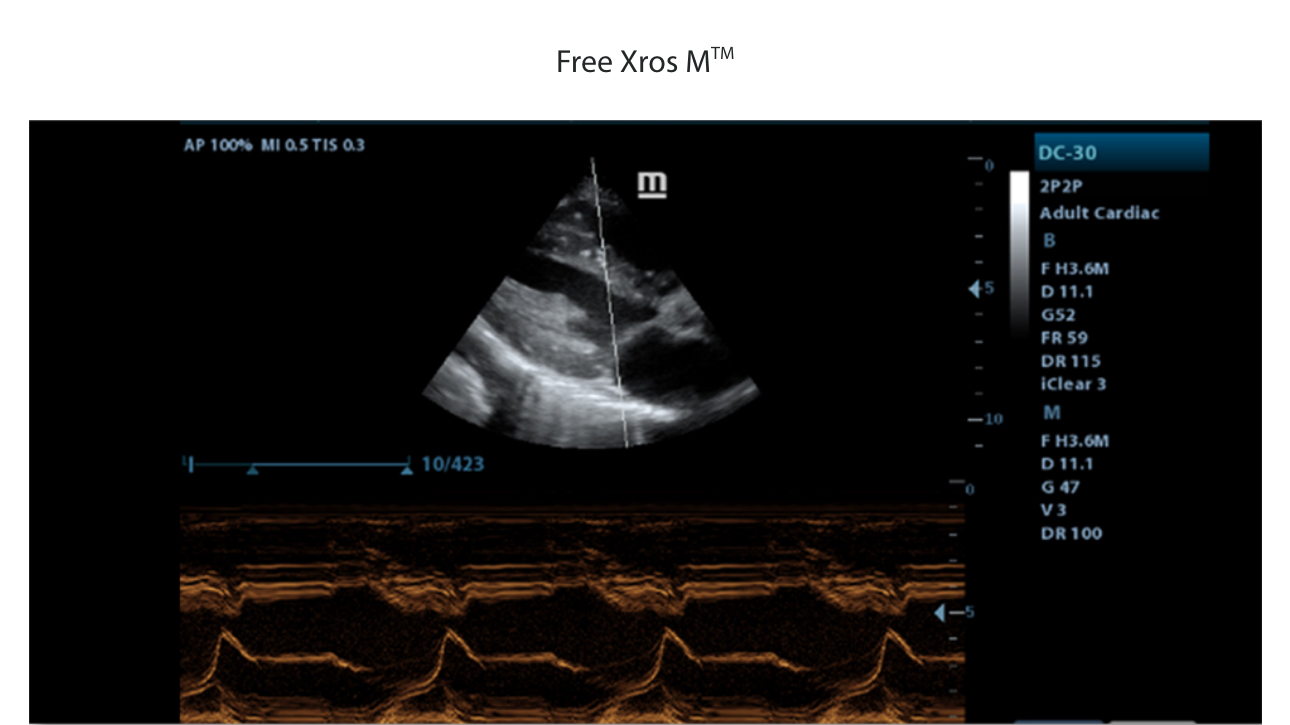

Hogere betrouwbaarheid:

Higher Reliable Dependence:

iScanHelper

iScanHelper

Ruime keuze aan toepassingsspecifieke onderzoeksvlakken

1

Vlakpakketten voor verschillende toepassingen: Abdomen, verloskunde/gynaecologie, schildklier, borst, testikel.

Incluindo diferentes (m├║ltiplos) modos de imagem.

Anatomische illustraties

2

Normale anatomische illustraties met inbegrip van schematische beelden en ultrasoundbeelden.

Zijdelingse weergave van een standaard ultrasonogram dat visuele aanwijzingen geeft over de relevante gebieden.

Standaard ultrasoundbeelden

3

Vergelijking realtimescan ter referentie.

Anatomische illustraties

4

Scanreferentiebeelden

5

Scanreferentiebeeld dat de juiste pati?ntpositie en sondeplaatsing laat zien.

Klinische beelden